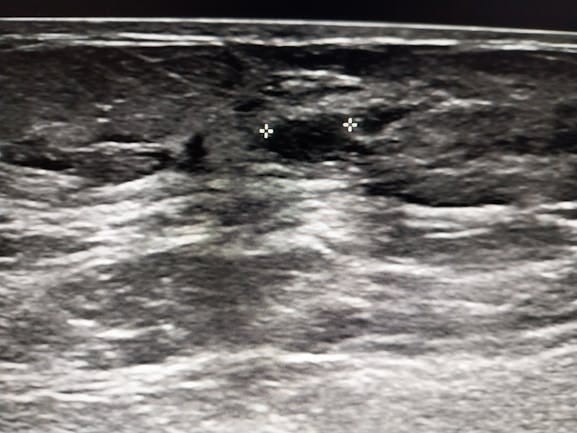

When I take your foot x-ray and post it to get clinical feedback, that’s considered disclosing protected health information. Even if the intention is good, I need direct patient consent.

This makes the work much harder. Because now I am exposed to risk and have to find my patient and not only get their permission but I have to get permission from my medical group to use the image which was taken on their premises.